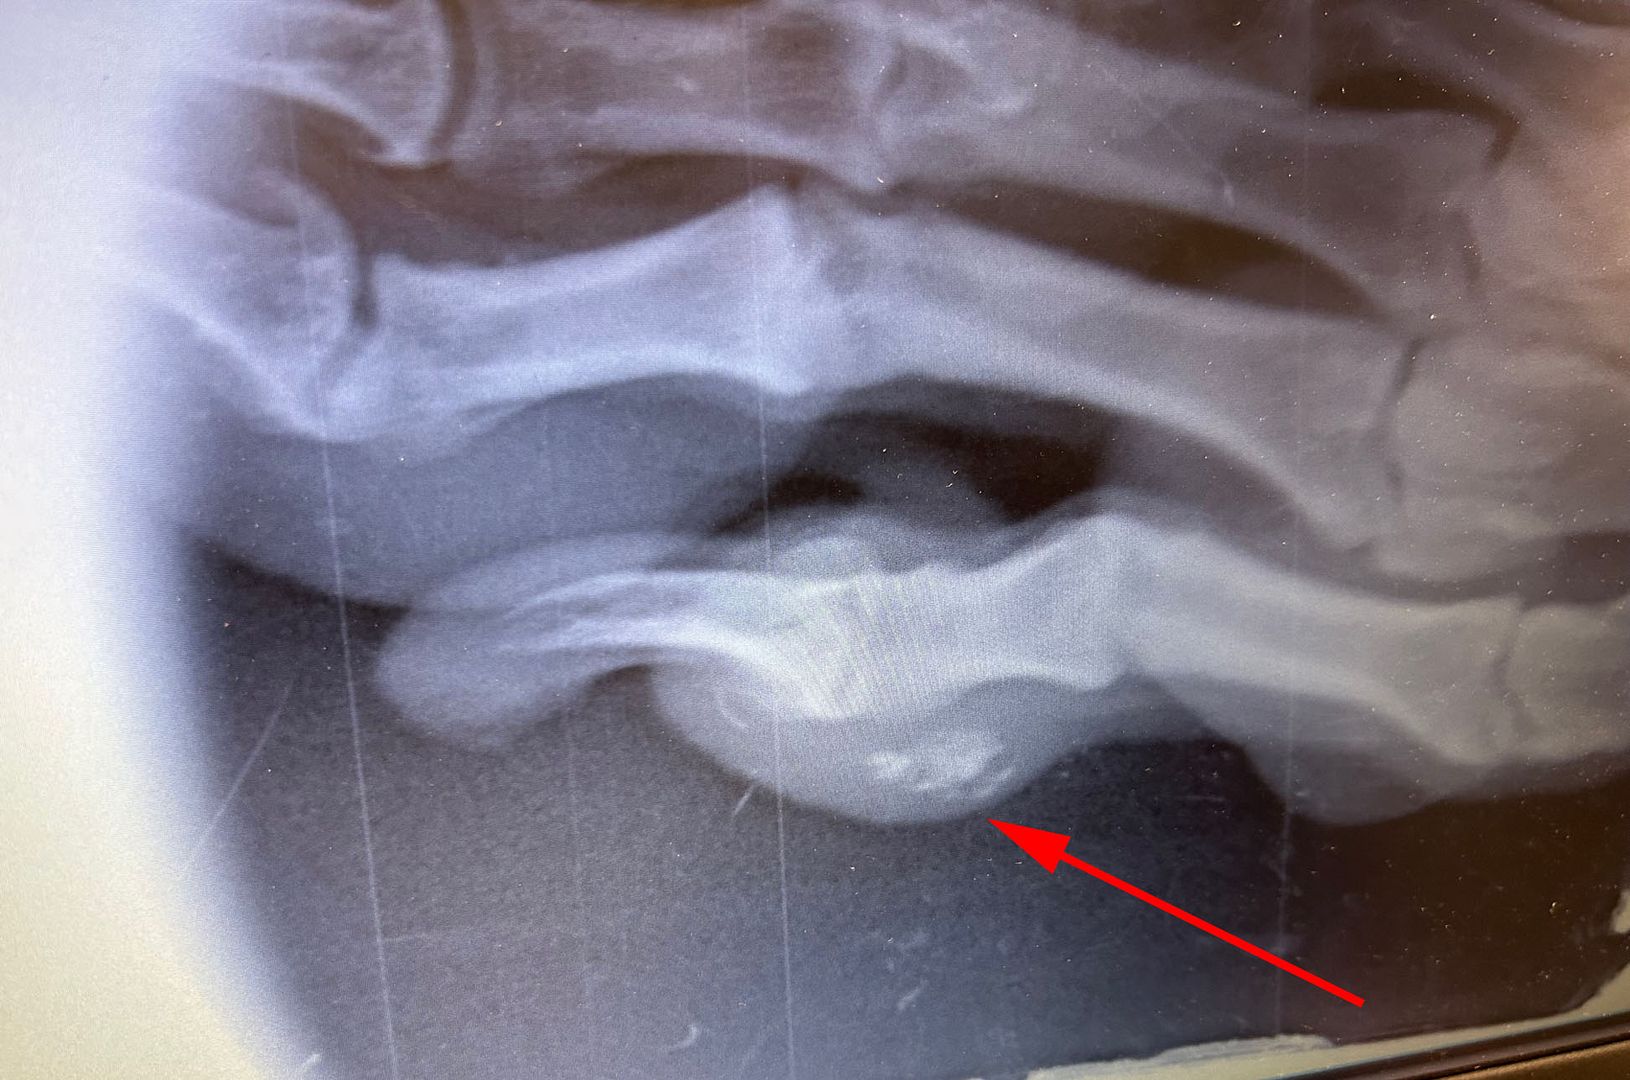

She had surgery on one of her foot pads to remove debris - here are the x-rays:

She had an intermittent limp that just wouldn't go away, and although there was a small puncture wound on her pad, I couldn't find anything in it (I often remove partially imbedded rocks from her pads). The vet didn't either the first time he looked at it, but when it didn't go away we took he back and they did the x-rays.

Yes. They were able to use dental x-rays to quickly see the issue...